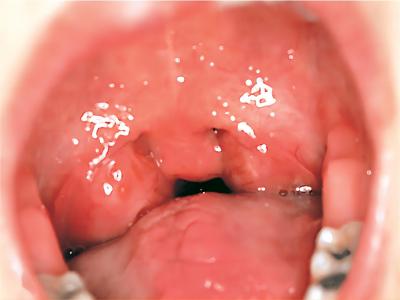

扁桃体

肿

急性隐窝性扁桃体炎扁桃体肿起来特别大图

急性隐窝性扁桃体炎患者在进行检查时,会发现扁桃体两侧明显发红,同时肿胀情况较为严重,病情较严重者会堵塞咽喉部位,容易出现进食困难的情况。